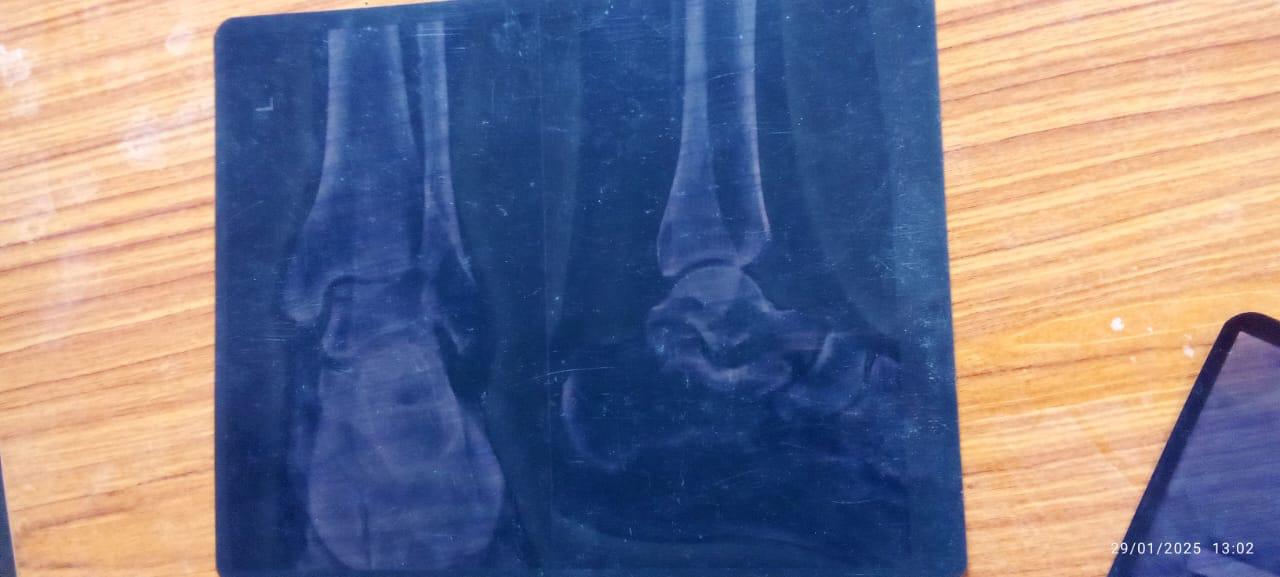

Help Ravi Shankar Stand Again: Support His Medical Recovery & Family’s Future

Ravi Shankar, the backbone of his family, is facing a life-altering challenge after a severe leg injury. He is in urgent need of financial assistance to cover medical expenses, including surgery, rehabilitation, and ongoing treatment. His family, dependent on his earnings, is struggling to meet daily needs. With your generous support, we can help Ravi regain mobility, stand on his feet again, and ensure his family doesn’t suffer. Every contribution, big or small, will bring him closer to recovery and give his loved ones hope for a better tomorrow. Let’s unite and make a difference in his life.